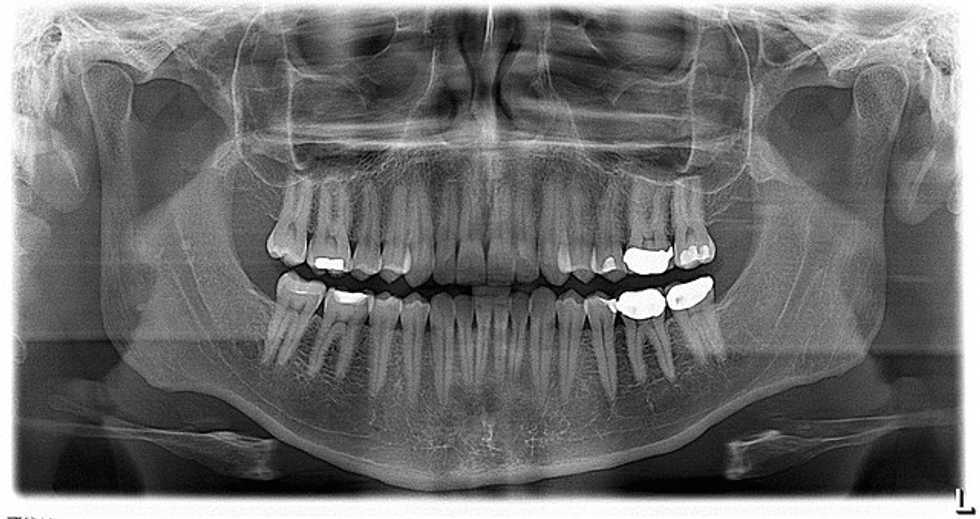

Photo: Eric Schmuttenmaer via Flickr